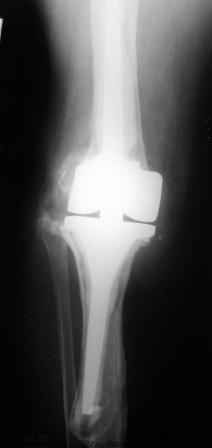

Уважаемые коллеги!Хотелось бы услышать Ваше мнение о возможности и способе помощи больной. 1939 г.р. В 1995г. эндопротезирование правого коленного сустава протезом Феникс, в 1999г. в г. Томске - ревизия - ротационный хинч W.Link. C 2005г. прогрессирует варусная деформация за счетнестабильности тибиального компонента. Попытка ортезирования - без эффекта. Попытка направить в ФСМУ без эффекта, да и больная не хочет никуда ехать.С уважением, Leonid

Понятно что для решения на операцию артродеза необходимы веские причины. Но я не уверен что здесь асептическое расшатывание. Судя по снимкам, бедренный компонент стоит не плохо, и есть рассасывание костной ткани вокруг всего протеза в голени. Что-то мне подсказывает об инфекционном процессе, возможно вялотекущем. В наших условиях я сделал бы обследование включающее анализы крови с СОЭ, СРБ. Сделал бы пункцию коленного сустава или даже биопсию мягких тканей для посева и микроскопии.

Изотопное сканирование с технецием и с мечеными лейкоцитами. PET-CT. И после этого легче принять решение. Если есть инфекция, то необходимо выполнить лечение этапное в котором первый этап удаление протеза и установка цементного спейсера с лечением АБ 6-8 недель. Если победите инфекцию, что видно по показателям СРБ и СОЭ, то через 3-6 месяцев можно вернуть протез.